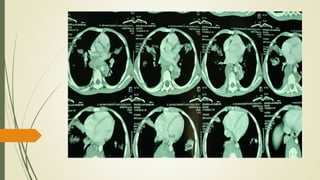

Chest CT scan done on 15/3/19

Chest CT scandone on 15/3/19